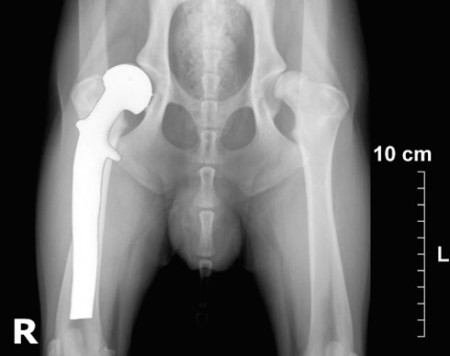

Inicio > Fotogalería: IMAGENOLOGIA > radiografia de cadera.jpg